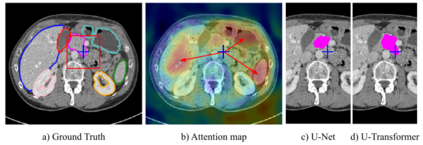

Medical image segmentation remains particularly challenging for complex and low-contrast anatomical structures. In this paper, we introduce the U-Transformer network, which combines a U-shaped architecture for image segmentation with self- and cross-attention from Transformers. U-Transformer overcomes the inability of U-Nets to model long-range contextual interactions and spatial dependencies, which are arguably crucial for accurate segmentation in challenging contexts. To this end, attention mechanisms are incorporated at two main levels: a self-attention module leverages global interactions between encoder features, while cross-attention in the skip connections allows a fine spatial recovery in the U-Net decoder by filtering out non-semantic features. Experiments on two abdominal CT-image datasets show the large performance gain brought out by U-Transformer compared to U-Net and local Attention U-Nets. We also highlight the importance of using both self- and cross-attention, and the nice interpretability features brought out by U-Transformer.